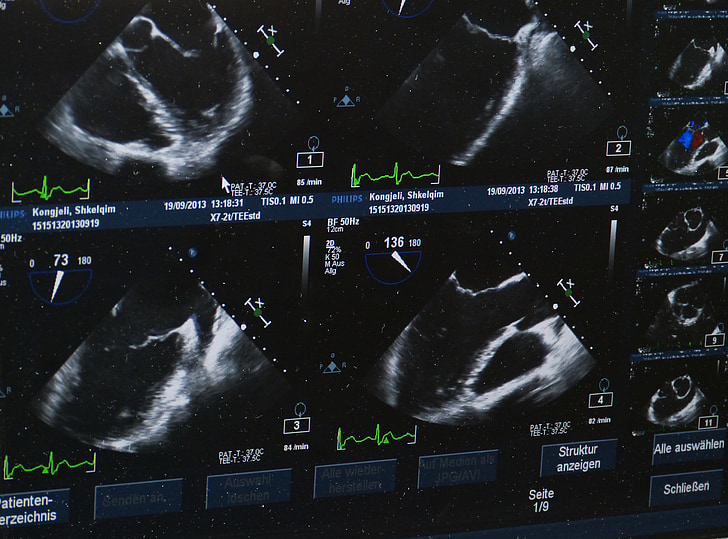

Chụp CT sọ não, còn được gọi là chụp cắt lớp vi tính sọ não, là phương pháp chẩn đoán hình ảnh hiện đại giúp bác sĩ kiểm tra các bất thường bên trong hộp sọ một cách rõ ràng và chi tiết. Kỹ thuật này sử dụng tia X quét từ cằm đến đỉnh đầu để thu thập hình ảnh các cấu trúc trong não bộ. Đặc biệt, đầu đèn phát tia của máy chụp CT có thể nghiêng theo nhiều hướng nhằm thu được các lát cắt khác nhau. Những dữ liệu này sau đó được lưu trữ trên hệ thống máy tính, cho phép tái tạo hình ảnh 2D, 3D và in ra phục vụ chẩn đoán.

Trong một số trường hợp, bác sĩ có thể chỉ định chụp CT sọ não có tiêm thuốc cản quang qua đường tĩnh mạch. Thuốc cản quang giúp làm nổi bật các vùng bất thường bằng cách tăng độ tương phản giữa mô não khỏe mạnh và các tổn thương, từ đó hỗ trợ phát hiện các vấn đề như tắc nghẽn mạch máu, khối u, viêm hay áp-xe não.

Chụp CT sọ não cho ra hình ảnh có độ phân giải cao, giúp bác sĩ quan sát rõ ràng cấu trúc bên trong hộp sọ. Các hình ảnh có thể được tái tạo dưới dạng 2D, 3D hoặc in ra tùy theo nhu cầu chẩn đoán.